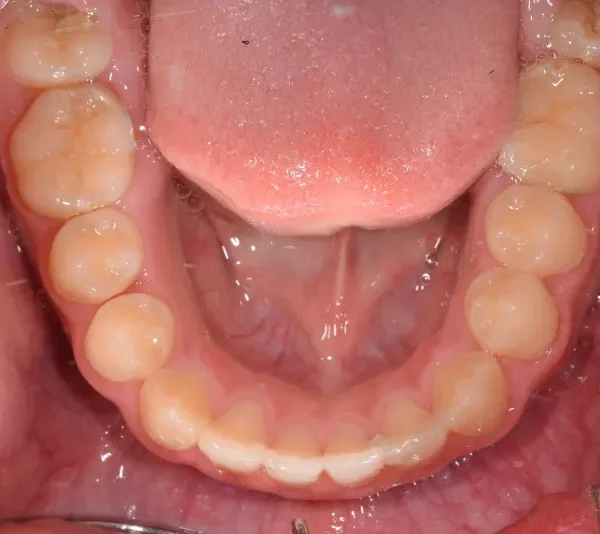

初診時年齢 小学校3年生 (男性) 主訴 前歯がゆがんでいる・ガタガタ

診断名 叢生・交叉咬合 装置名

上下の幅が狭くガタガタに生えています。

乳歯があるうちはオリジナル矯正装置を使用しました。

永久歯に生え変わってからはマルチブラケット装置を使用し、噛み合わせ・見た目をしっかり仕上げました。